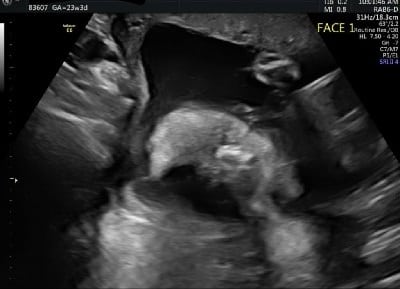

Ultrasound Photos at 23 Weeks Pregnant With Twins